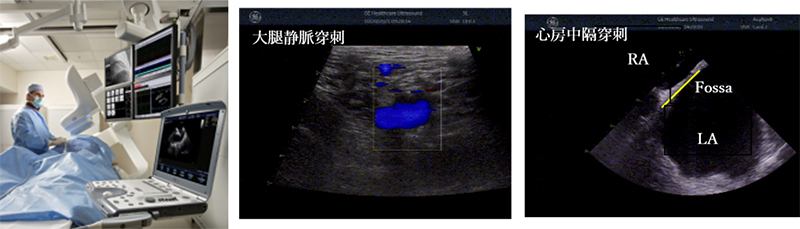

Prucka_tsukuba_04.jpg

CardioLabシステムは最大224極112chの心内電位を含む128chのレコーディング機能や各社のアブレーション装置、心臓刺激装置ならびに3Dマッピング装置とのCARTOインターフェイス機能等、ハイエンドのアブレーション治療支援に要求される機能を備えたシステムである。当院でCardioLabシステムを使用する際、カテーテルアブレーション・植込みデバイス治療で使用している。本装置に搭載されているカーディオICEインターフェイスはCardioLabシステムの画面に超音波診断装置(Vivid-i・S-70)のリアル画像を取り込むことができる。当院では主に穿刺時や肺静脈隔離術(PVI)、心室頻拍症例(VT)においてを超音波診断装置(Vivid-i・S-70)のリアル画像心房中隔穿刺(Brockenbrough)時にLabシステムの画面に表示させ使用している。